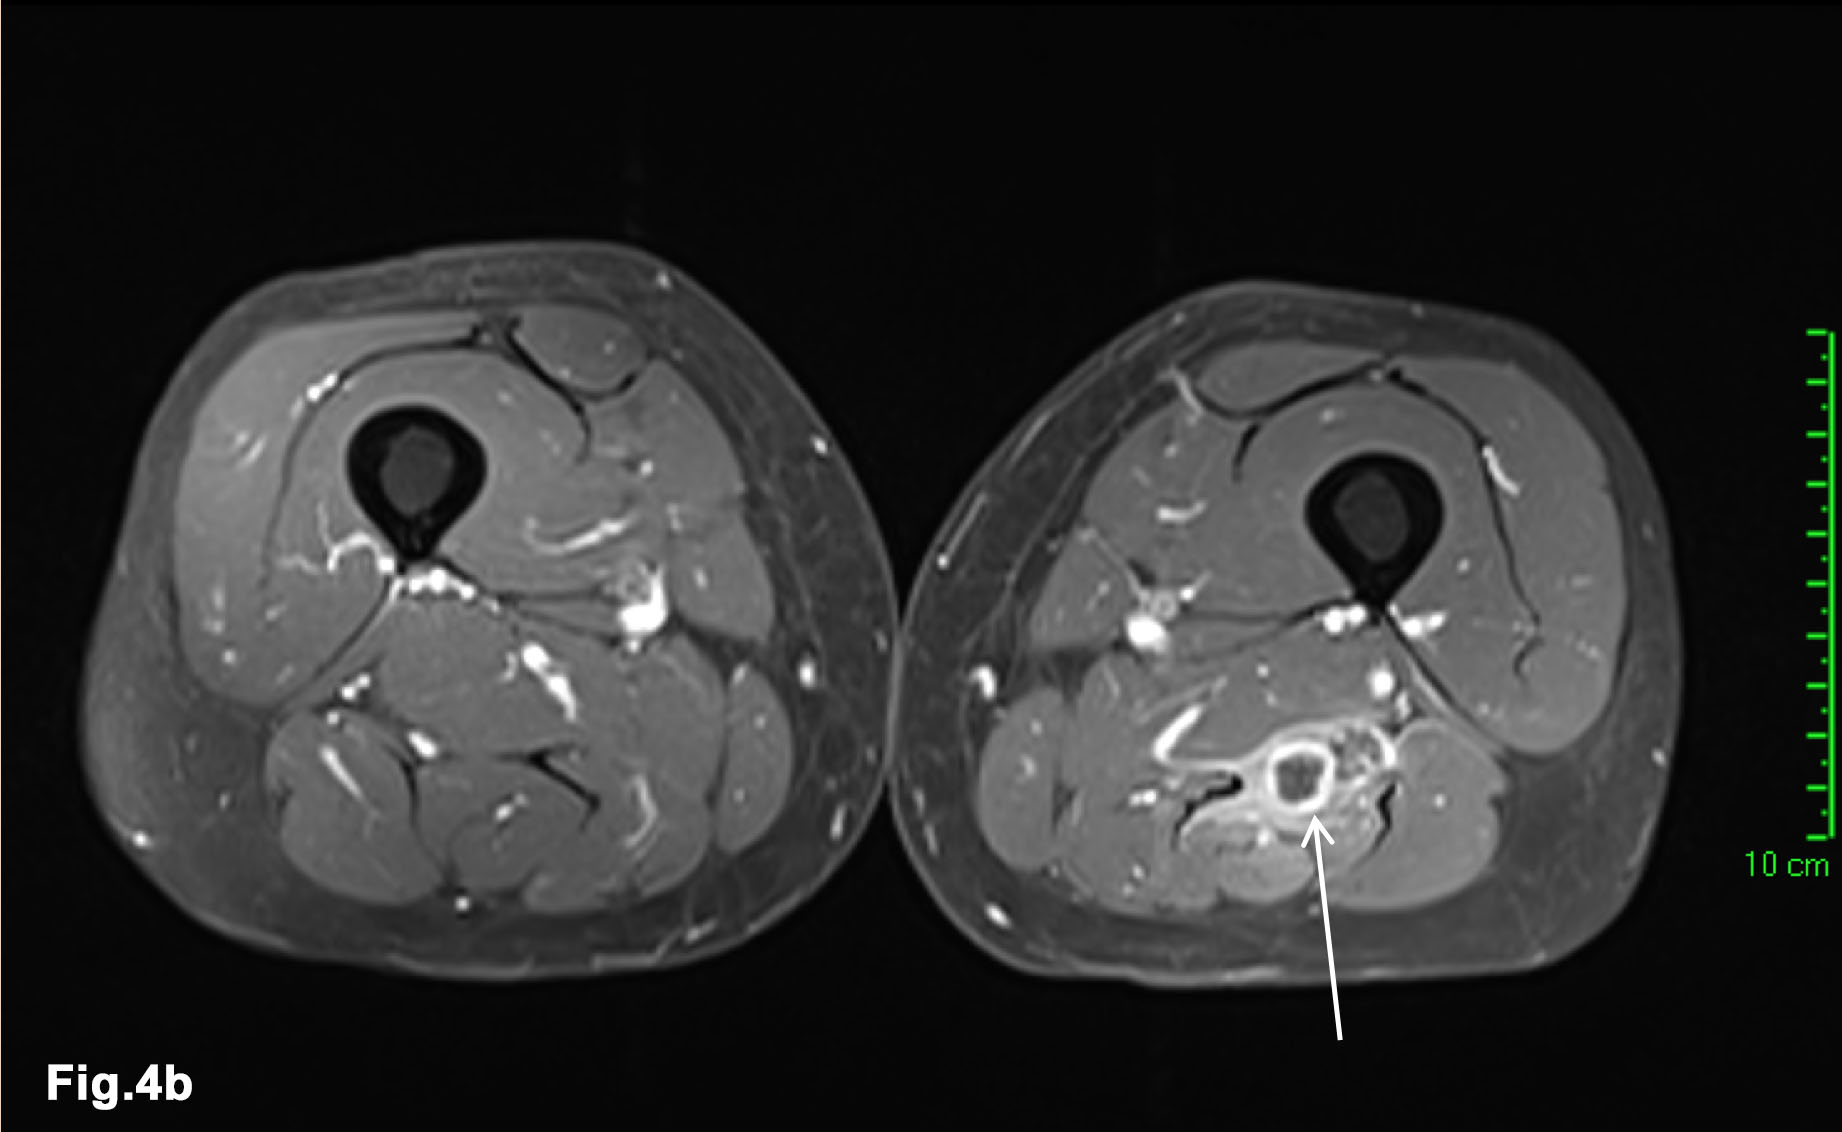

- MRI 2017- post chemotherapy (Figure 4)

- Both muscle lesions showed a significant reduction in size

Figure 2 – initial external MR - confirms larger mass within right distal biceps femoris muscle (solid arrow) and demonstrates further, smaller mass between fat plans of left posterior thigh muscles (line arrow) - T1w and PDW DRI images (Fig 2a) - T1W FS Gadolinium enhanced MR – demonstrates enhancing intramuscular lesions with peripheral oedema (arrows) (Fig 2b)